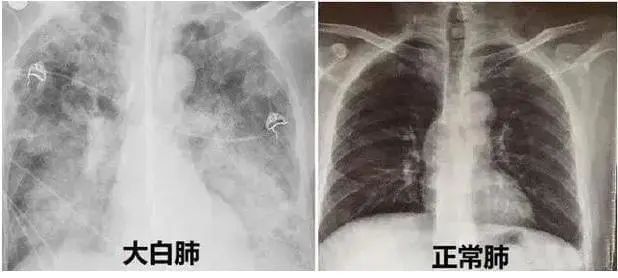

新冠后的“白肺”焦慮,如何早診斷早治療?

近期,多地醫(yī)生發(fā)現(xiàn)患者出現(xiàn)肺炎或白肺癥狀,引發(fā)關(guān)注。那么什么是白肺呢?其實(shí)白肺是肺部影像學(xué)表現(xiàn)的一個(gè)口語化描述。當(dāng)出現(xiàn)炎癥和感染,肺泡被滲出液等填充,在影像學(xué)上的表現(xiàn)就是出現(xiàn)白色區(qū)域。并不是只要肺部出現(xiàn)了炎癥就都叫白肺,一般來講肺部炎癥較重、滲出液較多,白色的影像區(qū)域面積達(dá)到70%?80%時(shí),在臨床上把它稱為白肺。通過“啄醫(yī)生”可以準(zhǔn)確地識別新冠肺炎的典型白肺影像,以下選取幾例最新病例加以說明。

胸片顯示整個(gè)雙肺已經(jīng)白化